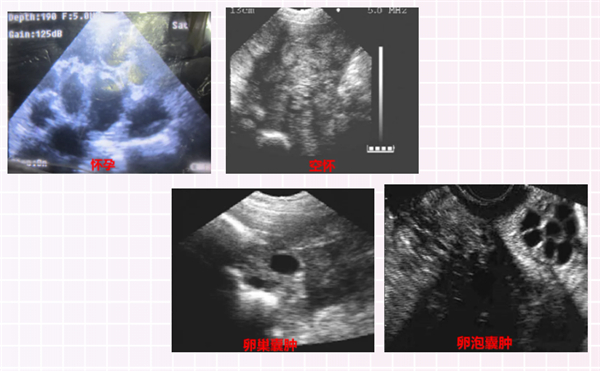

04 空怀母猪

空怀母猪指的是通过B超检查发现没有妊娠的母猪。

28天左右孕检,技术员误判怀孕导致怀孕后期出现空怀母猪。